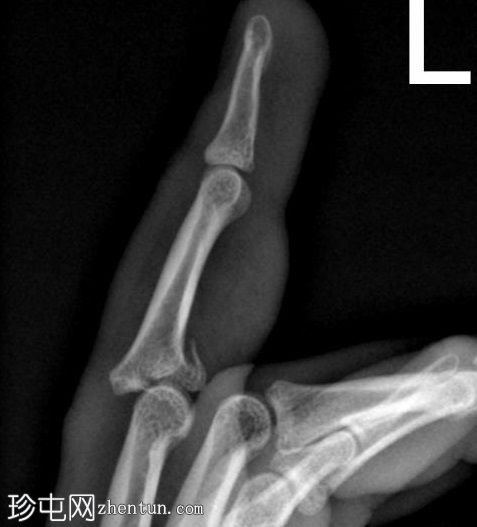

左

手外

伤。

X线片

侧位

可见第三指中节指骨基底部轻微移位骨折,延伸至近端指间关节(PIP关节),并伴有软组织肿胀。

第三指中节指骨基底部轻微移位骨折,延伸至近端指间关节(PIP关节)指骨,并伴有软组织肿胀。